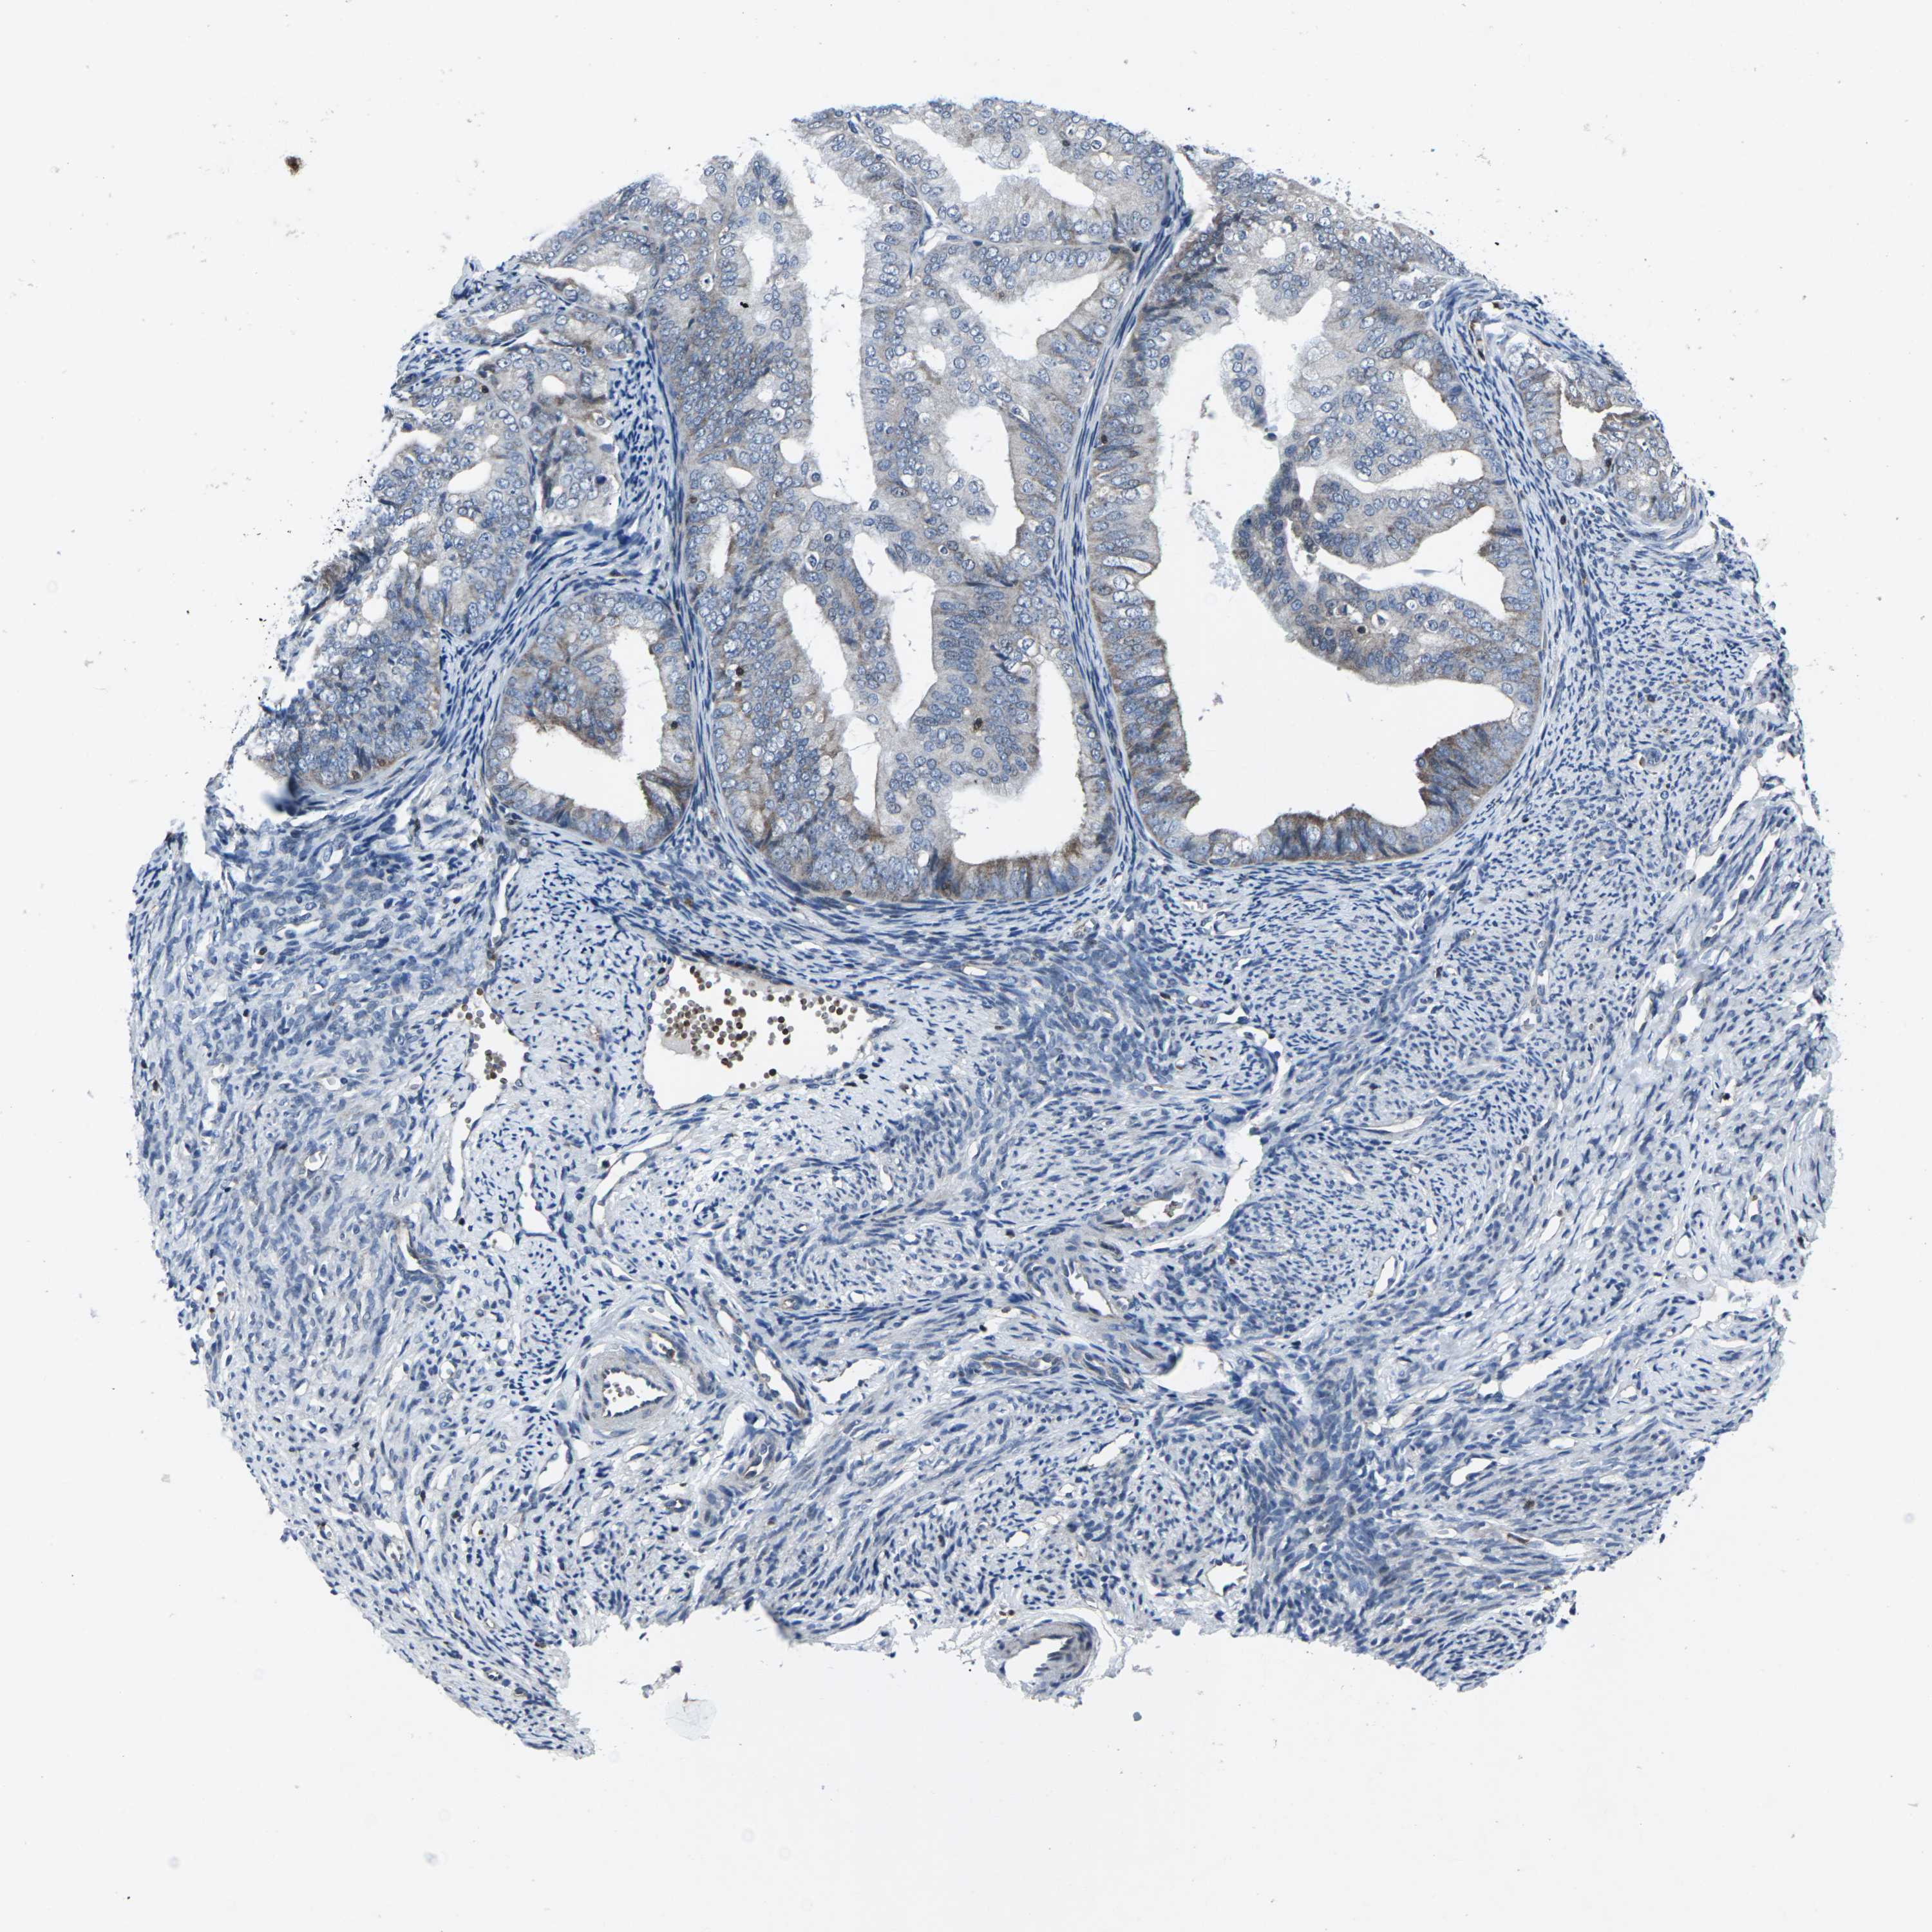

ENDOMETRIAL CANCER - Protein expressioni

A mouse-over function shows sample information and annotation data. Click on an image to view it in a full screen mode. Samples can be filtered based on level of antibody staining by selecting one or several of the following categories: high, medium, low and not detected. The assay and annotation is described here.

Note that samples used for immunohistochemistry by the Human Protein Atlas do not correspond to samples in the TCGA dataset.

Antibody stainingi

Antibody staining in the annotated cell types in the current human tissue is reported as not detected, low, medium, or high, based on conventional immunohistochemistry profiling in selected tissues. This score is based on the combination of the staining intensity and fraction of stained cells.

Each image is clickable and will lead to virtual microscopy that enables deeper exploration of all samples and also displays staining intensity scores, fraction scores and subcellular localization as well as patient and tissue information for each sample.

Antibody HPA001860

Antibody CAB013108

Staining

High

Medium

Low

Not detected

Intensity

Strong

Moderate

Weak

Negative

Quantity

>75%

75%-25%

<25%

None

Location

Nuclear

Cytoplasmic/membranous

Cytoplasmic/membranous,nuclear